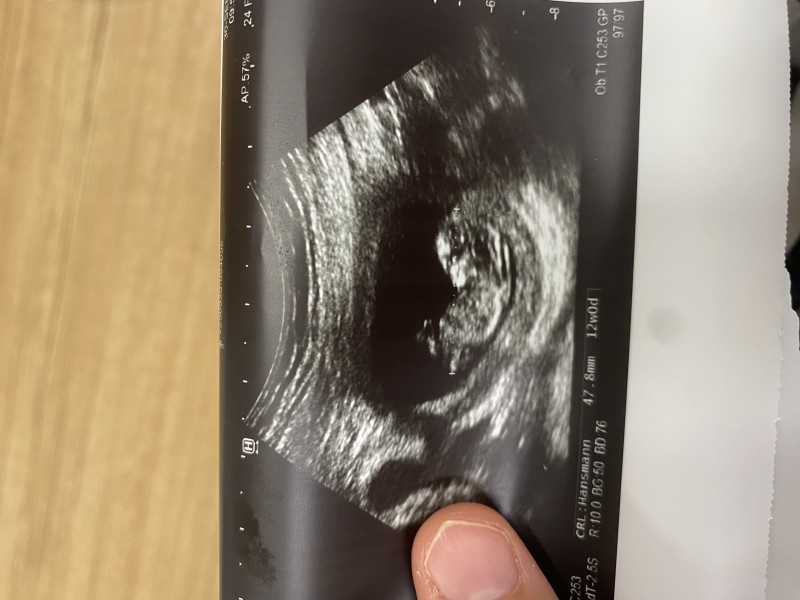

Kızlar merak edenler atsın 7 8 haftalık 15 16 hafta fark etmez gönderin gelisn tahminde bulunayım. Sosyal medyada kadınlar parayla yapyır insanı sömürmekten başka bir şey değil. yüzde 50 yüzde 50 ihtimali olan bir şey rabbim öncelikle sağlık versin. Daha önce baktıklarım göre göre doğru cıktı şimdi merak dindirme için bakalım ne cıkacak :)))

image

gec oldu ama tahmin bekliyorum

Erkek gibi geldi cnm.ama emin de degilim yine de cok heveslenme:) sadece bir tahmin. Ogrenince yaz lutfen

Ya ben 12 haftalık gebeyim ama o kağıtlardan hiç birşey anlamıyorum bebek kağıdın neresinde onu bile anlamıyorum :) eve gidince atayım kız

Bu arada cinsiyeti kız gibi geldi bana hayırla kucağına al inşallah